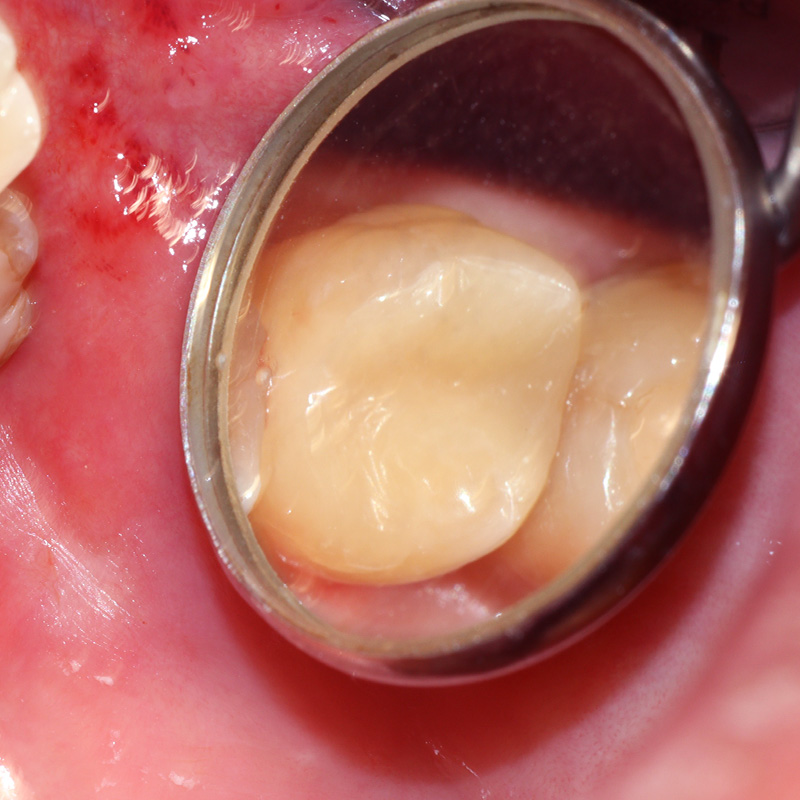

Результаты лечения глубокого кариеса на фото до и послеСмотреть работуСрок лечения:1 визитСумма лечения:6 820 р.